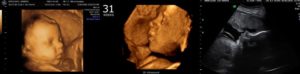

Если снимки выполняют посредством 3D УЗИ, то на фотографии можно рассмотреть радужную оболочку глаза.

Что интересно — на сроке 31 неделя беременности при УЗИ на фото и видео уже можно достаточно подробно рассмотреть черты лица ребенка.

Конечно, цвет глаз еще не рассмотреть (хотя радужная оболочка в этот период уже начинает приобретать свойства взрослого глаза и реагирует на яркий свет), но сейчас все более популярной становится технология 3D и 4D УЗИ, которая дает наибольшие возможности в визуализации плода.